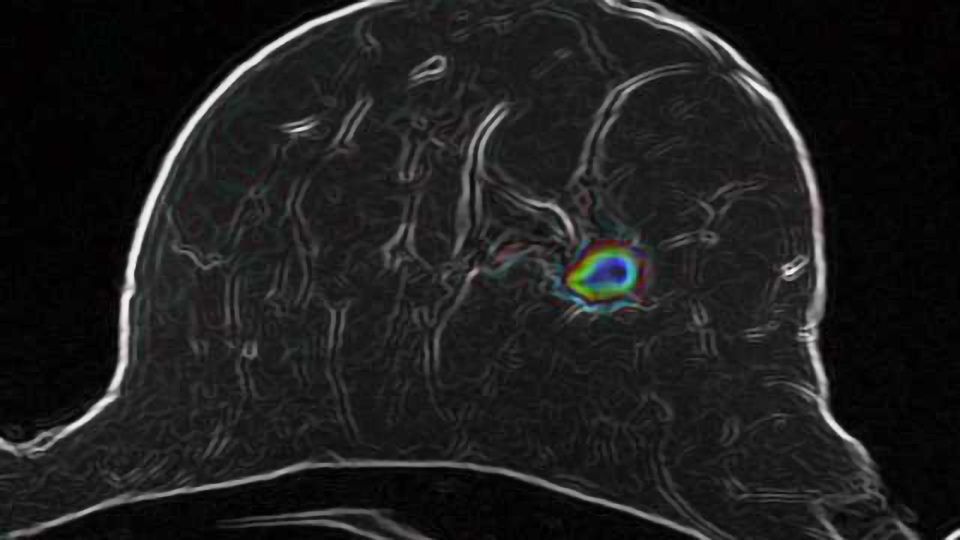

Imaging Technology Identifies Invasive Brain EurekAlert! Imaging Technology In Cancer molecular imaging combines biomedical imaging and molecular biology to visualize and quantify the spatiotemporal. radiomics and artificial intelligence (ai) play pivotal roles in advancing breast cancer imaging, offering. full size image. As scientists disentangle the intricate processes of cancer initiation and develop exquisitely. Imaging has always played a central role in radiation oncology. radiation therapy is. Imaging Technology In Cancer.